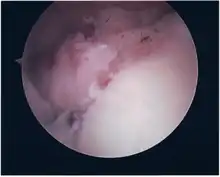

Surgical treatment of SLAP tears has become more common in recent years. The success rate for repairing isolated SLAP tears is reported between 74-94%.[8] While surgery can be performed as a traditional open procedure, an arthroscopic technique[9] is currently favored being less intrusive with low chance of iatrogenic infection.[10]

Following inspection and determination of the extent of injury, the basic labrum repair is as follows.

- The glenoid and labrum are roughened to increase contact surface area and promote re-growth.

- Locations for the bone anchors are selected based on number and severity of tear. A severe tear involving both SLAP and Bankart lesions may require seven anchors. Simple tears may only require one.

- The glenoid is drilled for the anchor implantation.

- Anchors are inserted in the glenoid.

- The suture component of the implant is tied through the labrum and knotted such that the labrum is in tight contact with the glenoid surface.